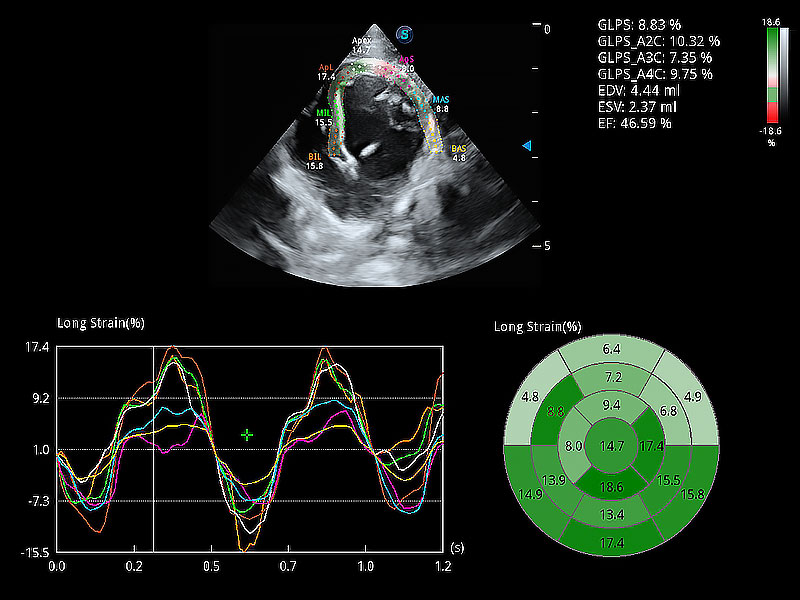

• MQA 心肌定量分析

通過心肌識別技術(shù)與二維斑點追蹤技術(shù)相結(jié)合,對心臟的超聲圖像進(jìn)行量化分析。計算心肌17個節(jié)段的應(yīng)變、應(yīng)變率、速度、位移等,并通過牛眼圖的形式進(jìn)行呈現(xiàn)。

(犬)四腔心MQA